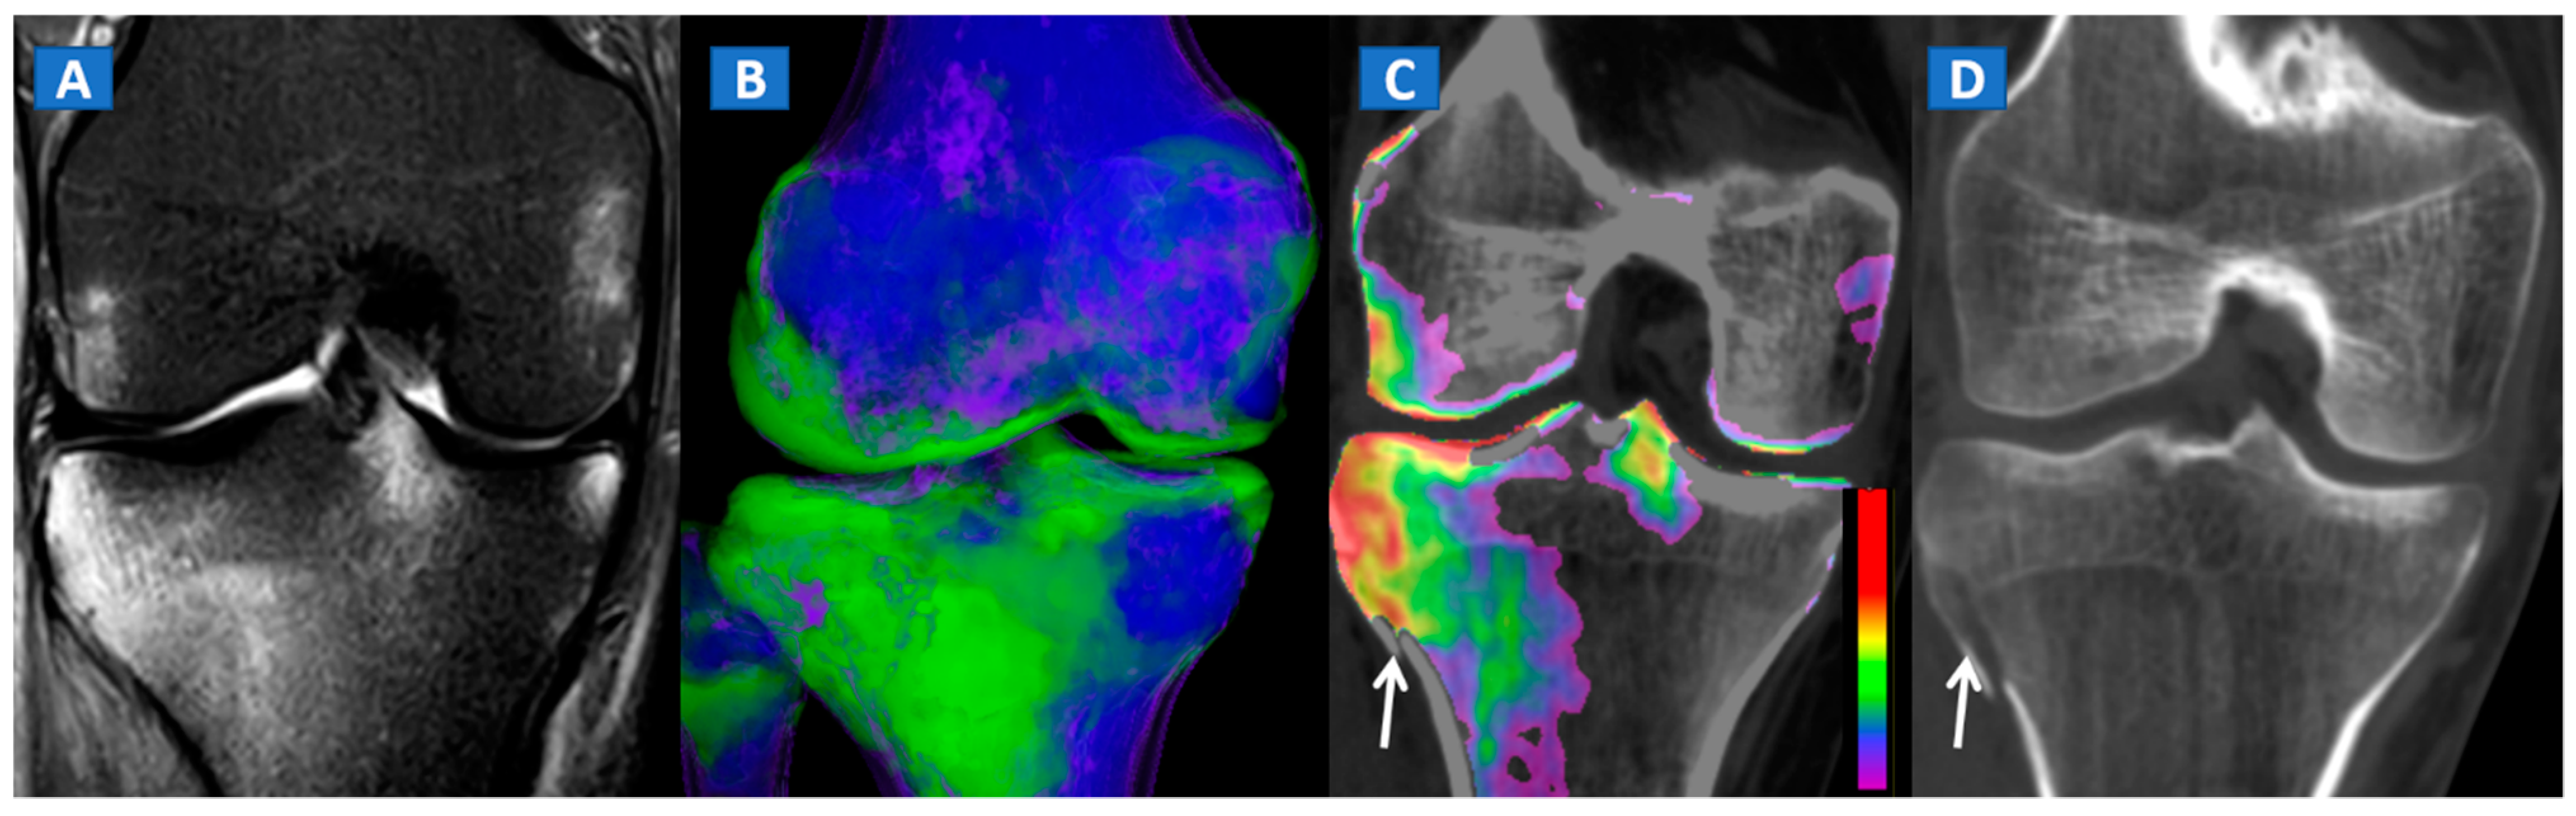

Figure 5.

A 34-year-old male with a post-traumatic avulsion fracture of the lateral aspect of the proximal tibia. On the coronal STIR MRI image (A), multiple BME foci can be identified on the lateral aspect of the proximal tibia. On the coronal 3D DECT image (B), the distribution of BME foci is confirmed. On the corresponding 2D 1 mm reconstructed 2D DECT image (C), the BME appears more pronounced on the lateral aspect of the proximal tibia, adjacent to a cortical defect (arrow). The corresponding standard 1 mm reconstructed coronal CT image (D) confirms a minimally dislocated avulsion fracture (arrow).

Figure 6.

A 65-year-old female with a post-traumatic medial menisci rupture and diffuse BME. On the standard 1 mm reconstructed coronal CT image (A), there are no signs of fracture. On the corresponding 2D 1 mm reconstructed 2D DECT image (B), the BME appears more pronounced on the femoral condyles and on the medial tibial plateau (arrows). By using different color-coding (C), it was possible to identify a rupture of the medial menisci (straight arrow), with thickening and oedema of the medial collateral ligaments (curved arrow).